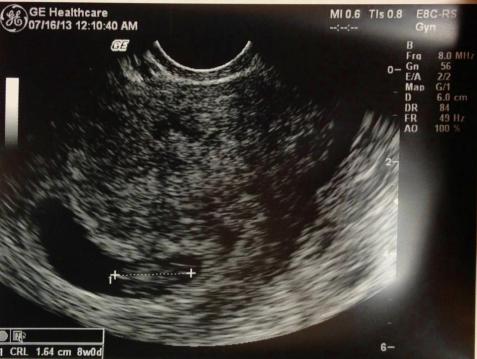

More ultrasounds with OB. I get to see the baby more often and possibly discover gender sooner.

I would see their perinatologist (who is supposed to be wonderful) for a Level II ultrasound.